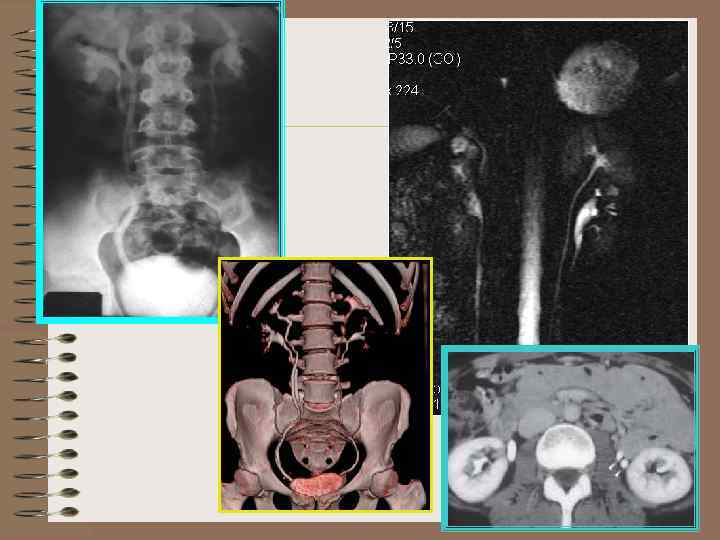

Удвоенная почка (УЗИ) • Увеличен только продольный размер • Паренхиматозная перегородка разделяет срединный эхокомплекс • «Зарубка» на наружной поверхности

Rg-признаки удвоенной почки • Увеличение продольного размера почки • Выпрямление оси почки • В нижней лоханке верхние чаши смещены вниз и кнаружи, «увядшая лилия» • Два мочеточника • При гидронефрозе верхней половины и отсутствии функции ЧЛС расположена экцентрично, ближе к нижнему полюсу

ВУ – удвоенная почка

Удвоенная почка